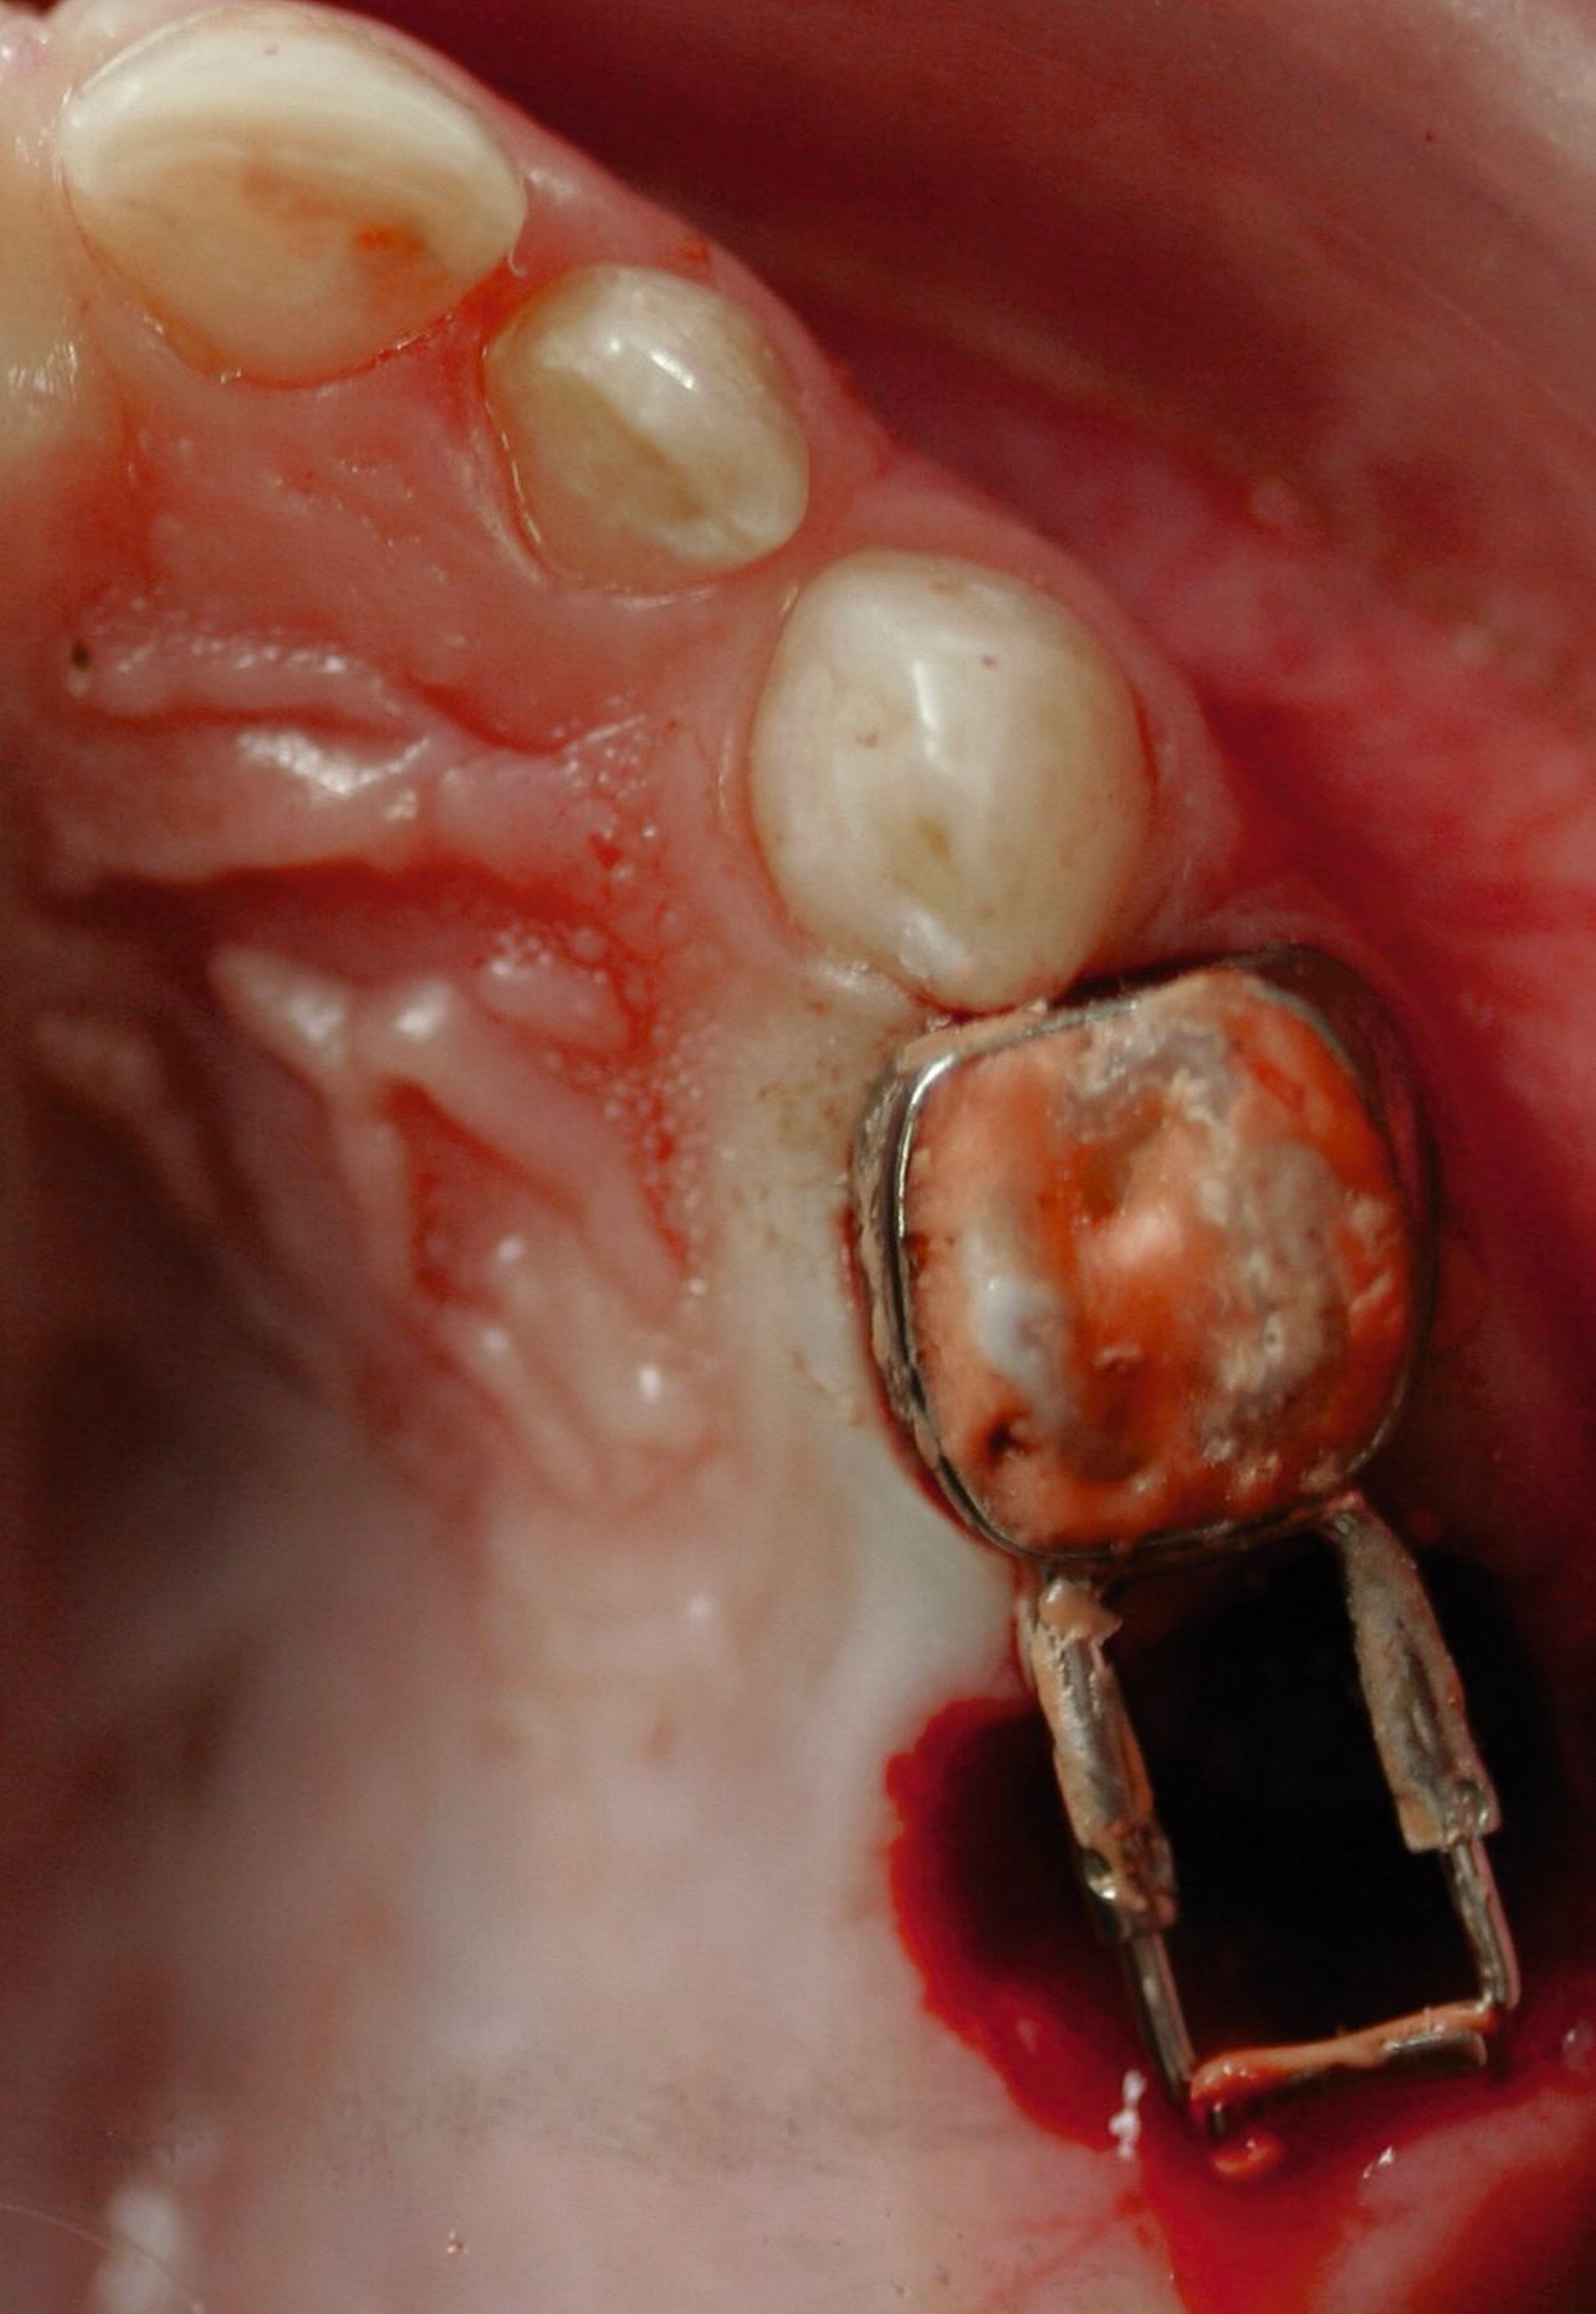

Gerade in der Kariesentfernung hat sich in den vergangenen Jahren eine bemerkenswerte Verschiebung ergeben: Die Hall-Technik hat erfolgreich gezeigt, dass bei einem dichten Verschluss eigentlich überhaupt keine Entfernung von kariös verändertem Schmelz oder Dentin notwendig ist. Auch bei der Kariesinaktivierung ist in der Regel keine Kariesentfernung nötig, gegebenenfalls ein Aufschleifen der Läsion zur besseren Reinigungsfähigkeit (Abbildung 3). Und selbst bei restaurativen Techniken wurde die Idee vom „sauberen, keimarmen Restdentin“ und zusätzlicher „Kavitätentoilette“ zur weiteren Keimreduktion verlassen und durch die selektive Kariesexkavation mit primär kariesfreien Kavitätenrändern zur adäquaten Verankerung einer Restauration ersetzt.

Die Kariesinaktivierung von approximal kariösen Läsionen bei Milchzähnen ist schwieriger, da diese in der Regel nicht gut für die tägliche Mundhygiene zugänglich sind. Daher können diese Läsionen für eine Kariesinaktivierung in der Zahnarztpraxis oberflächlich rotierend eröffnet werden (Abbildung 3), um dort eine manuelle Plaqueentfernung durch das Zähneputzen und Fluoridierungen zu Hause beziehungsweise in der Praxis zu ermöglichen. Ferner erhalten die Eltern exakte Mundhygiene- und Ernährungsinstruktionen sowie eine effektive Motivation zur entsprechenden Umsetzung. Das beinhaltet auch ein Putztraining und Anwendung von Techniken im Rahmen der sprechenden Zahnmedizin wie „motivational interviewing“ [Miller und Moyers, 2017]. Bei dieser nicht-restaurativen Kariestherapie wird im Gegensatz zu den Standardfüllungen das Kariesmanagement bewusst auf die Patientenebene verlagert, da nur durch die manuelle Störung des Biofilms (also das Putzen) der chronische Kariesprozess gestoppt werden kann und somit eine Inaktivierung von Karies erfolgt [Kidd und Fejerskov, 2013]. In diesem Falle ist nicht zwingend eine restaurative Therapie notwendig, kann aus ästhetischen oder funktionellen Gründen aber sekundär bei inaktiven Läsionen erfolgen.

Eine weitere wichtige Alternativmethode ist die Hall-Technik [Santamaria and Innes, 2018; Midani et al., 2019; Santamaría et al., 2020], die im Rahmen neuer biologischer Konzepte bereits vor einigen Jahrzehnten von Dr. Norna Hall in Schottland entwickelt wurde. Im Gegensatz zur konventionellen Stahlkronenversorgung wird bei dieser Technik auf Lokalanästhesie, Präparation und Kariesentfernung vollständig verzichtet. Stattdessen wird eine vorgefertigte Stahlkrone direkt auf den kariösen, pulpal asymptomatischen Milchmolaren zementiert (Abbildung 7). Die Hall-Technik hat in vielen klinischen Studien gezeigt, dass die klassische „Kariesentfernung“ nicht nötig ist, wenn die Restauration bakteriendicht und stabil platziert werden kann. Darüber hinaus gibt es SMART-Techniken (Silver Modified Atraumatic Restorative Technique), die die Anwendung von SDF mit minimalinvasiven restaurativen Verfahren wie der ART oder der Hall-Technik kombinieren. Bei der SMART-Technik wird nach der Kariesarretierung mit SDF entweder eine hochviskose Glasionomerzementfüllung (SMART) oder eine vorgefertigte Stahlkrone (SMART-Hall, Abbildungen 5b und 5c) eingesetzt. Diese Kombination verbessert die Prognose des Zahnes, vermeidet mögliche Frakturen und Platzverluste und trägt ästhetisch-funktionellen Ansprüchen besser Rechnung.